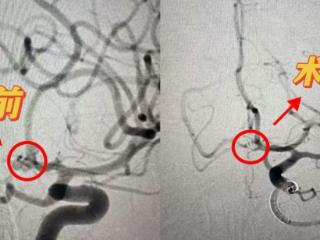

颅内动脉瘤破裂命悬一线 济南南郊医院脑科团队微创栓塞保平安